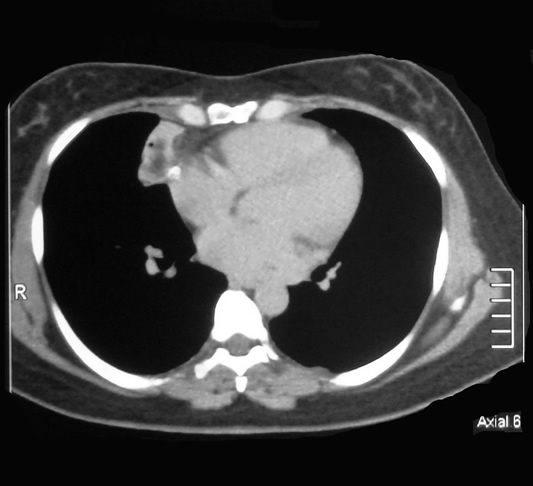

Corte Tomografico 06

Corte Tomográfico ventana Mediastinal

Sección transversal mas bajo, a nivel para cardiaco

La lesión redondeada en su menor diámetro, anterior a la  aurícula derecha, su forma se adapta al continente, hay un nódulo calcificado en el interior de la lesión.

Sección transversal mas inferior a la altura del cardias:

El corazón mantiene su conformación bien limitado.

la lesión en su menor dimensión se sitúa adosada al lado derecho del cardias.